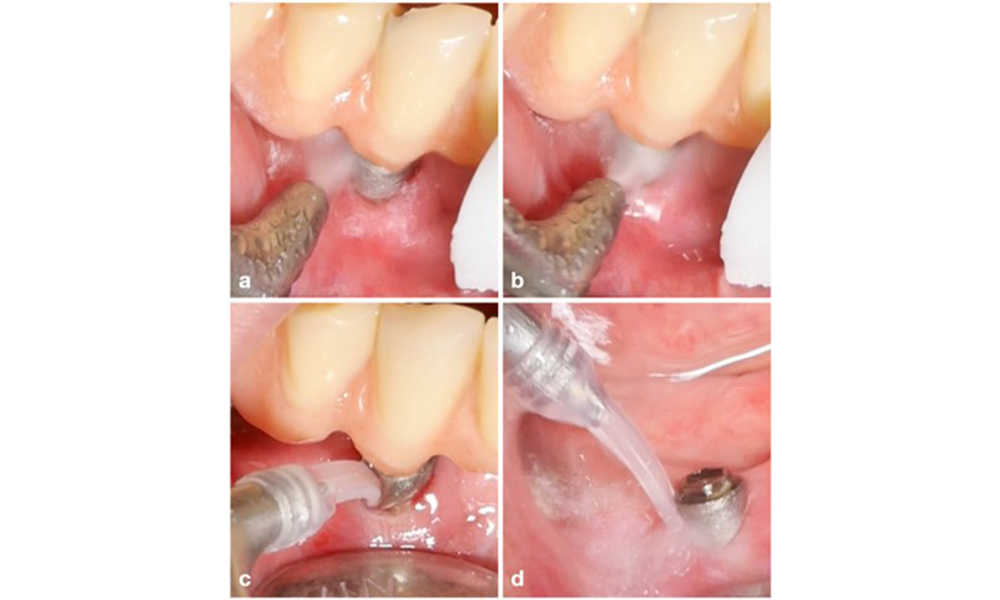

Patient case with peri-implant mucositis, poor oral hygiene and calculus accumulation (a). In such case the combination of different equipment is advisable, i.e., specially designed tips for ultrasonic scalers are necessary to remove the calculus (b), and an air-polishing device helps in removing remaining soft biofilm (c–d).

The choice of equipment depends on clinical circumstances, such as the distinction between calculus and soft plaque. Thus, in cases with calculus, titanium or plastic curettes, or specially designed tips for ultrasonic scalers should be used first, followed by the use of an air-polishing device (figure 7). In cases with only soft plaque accumulation, an air-polishing device alone can be sufficient. Air-polishing devices are operator and patient friendly and at least as efficient as standard instruments (Schwarz et al. 2015a).